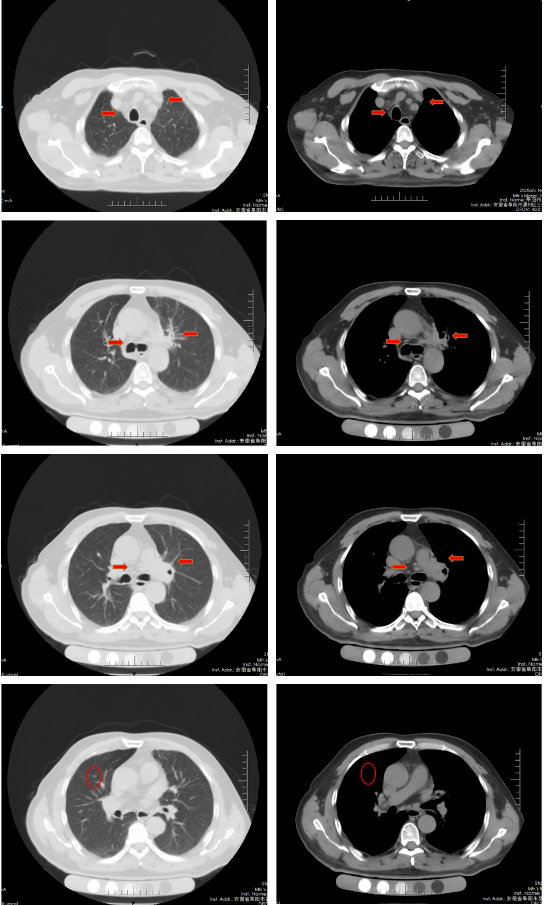

胸部增强CT(2022-02-12):左肺门及纵隔内见团块状软组织密度影,大小约62mm×42mm,边界不规整,内见血管影穿行,增强扫描呈轻度强化,局部支气管狭窄,远端肺内见片状磨玻璃密度影,边界欠清。右肺上叶见结节状密度增高影,较大直径约为8mm,增强扫描呈轻中度强化,右侧斜裂见长径约为6mm的高密度影,增强扫描未见明显强化;两肺透亮度增强,左肺下叶胸膜下囊状透光区。余气管、支气管通畅,未见明显狭窄、阻塞。纵隔和左肺门区见多发肿大淋巴结影,部分融合。两侧胸腔无明显积液。胸部CT诊断:左肺门及纵隔内占位,考虑肺Ca;纵隔及左肺门淋巴结肿大;右肺上叶结节,转移可能;右侧斜裂下结节;两肺肺气肿、左肺下叶肺大泡。

胸部CT(2022-04-12):左肺门及纵隔内见团块状软组织密度影,大小约57mm×37mm,边界不规整,局部支气管狭窄,远端肺内见片状磨玻璃密度影,边界欠清。右肺上叶见结节状密度增高影,较大直径约为9mm,右侧斜裂见长径约为7mm的高密度影;两肺透亮度增强,左肺下叶胸膜下囊状透光区;两肺可见索条状影。余气管、支气管通畅,未见明显狭窄、阻塞。纵隔和左肺门区见多发肿大淋巴结影,部分融合。两侧胸腔无明显积液。胸部CT诊断:左肺占位复查;纵隔及左肺门淋巴结肿大;右肺上叶结节,转移可能;右侧斜裂下结节;两肺肺气肿、左肺下叶肺大泡。

治疗后评价:经过EP方案治疗后两周期,患者仍有咳嗽、咳痰及左侧胸痛,症状无缓解,且出现体重下降;影像学检查提示左肺病灶及纵膈淋巴结及肺门淋巴结较前缩小不明显(缩小<30%),疗效评价SD。总体效果欠佳。

胸部CT(2022-07-15):双侧肺野透亮度增加,以两上肺和胸膜下明显。双肺纹理增多、增粗,紊乱,左肺上叶条片状高密度灶,大小约45mm×19mm,小叶间隔增厚。气管、左右主支气管无明显狭窄。纵隔内未见肿大淋巴结影。两侧胸腔无明显积液。胸部CT诊断:左上肺门占位复查;慢性支气管炎-肺气肿样改变。

治疗后评价:患者经过EP方案联合斯鲁利单抗治疗四周期后,患者咳嗽、咳痰及左侧胸痛症状消失,体重逐渐恢复;影像学提示左肺病灶及纵膈淋巴结及肺门淋巴结较前明显缩小(缩小>30%),右肺结节基本消失;疗效评价:PR(接近CR)。

胸部CT(2022-08-30):双侧肺野透亮度增加,以两上肺和胸膜下明显。双肺纹理增多、增粗,紊乱,左肺上叶见条片状高密度灶,大小29mm×18mm,小叶间隔增厚,两肺下叶见囊状透亮区。气管、左右主支气管无明显狭窄。纵隔内未见肿大淋巴结影。两侧胸腔无明显积液。胸部CT诊断:左上肺门占位复查;慢性支气管炎-肺气肿样改变;两肺下叶肺气肿。

治疗后评价:患者经过斯鲁利单抗单药维持治疗两周期后,患者未再出现咳嗽等症状,体重逐渐增加。影像学提示左肺病灶及纵隔淋巴结及肺门淋巴结、右肺结节基本消失,疗效评价接近CR。